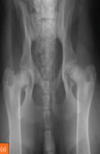

Fractures aren’t symmetrical so if the exact same mark is in the same spot in both limbs, consider nutrient foramens.

In the image: the thin dark lines. There is also a Mach line to the left of the nutrient foramen.